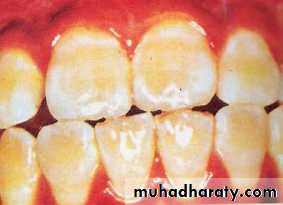

. MODERATE (3) All enamel

surfaces of the teeth are

affected and surfaces subject

to attrition show wear. Brown

stain is frequently a disfiguring

feature.